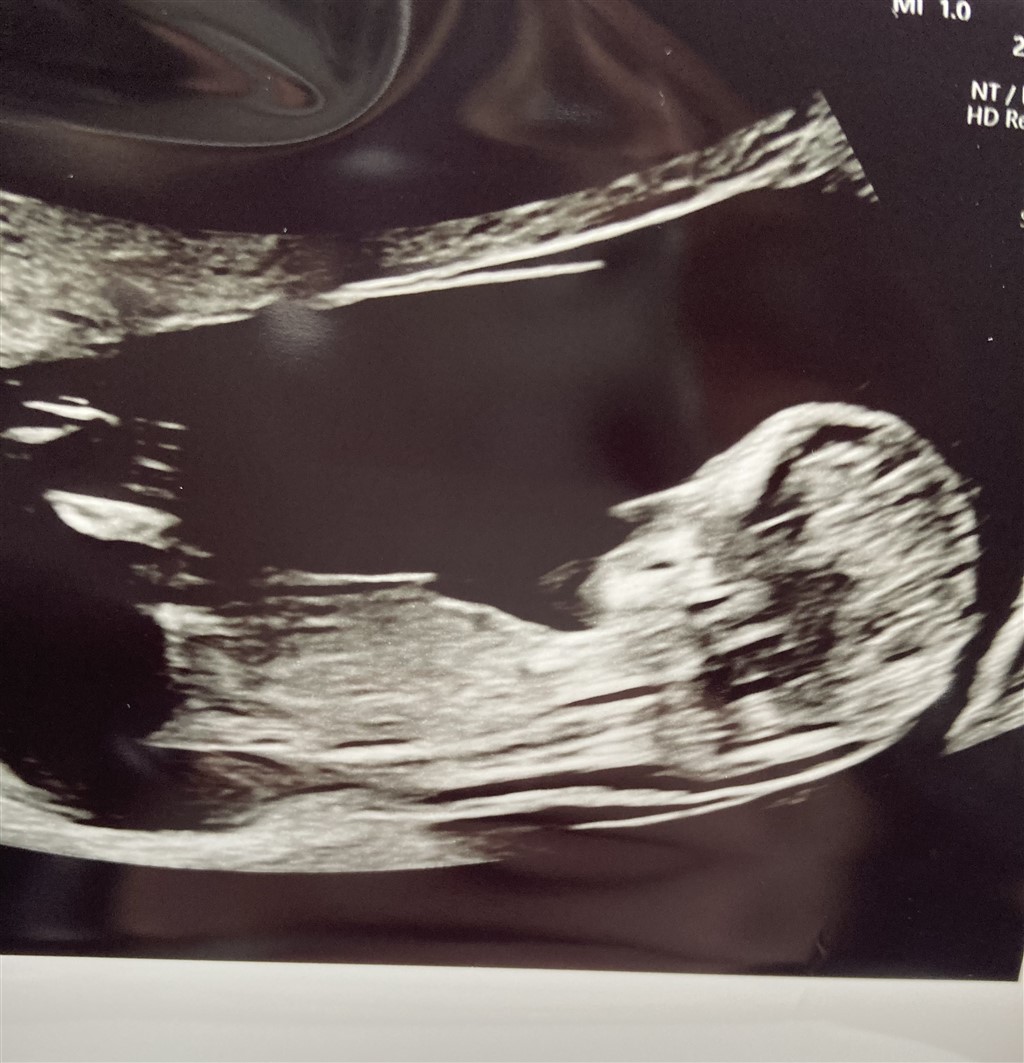

Ja så er der endnu en baby på vej. Bestemt ikke planlagt og lavet trods udebleven mens, men til verden dét vil den. Så velkommen det er den i hvertfald

Har været til nf som gik rigtig godt og måler baby til 12+5

Nogle gæt til hvad det kunne udvikle sig til?